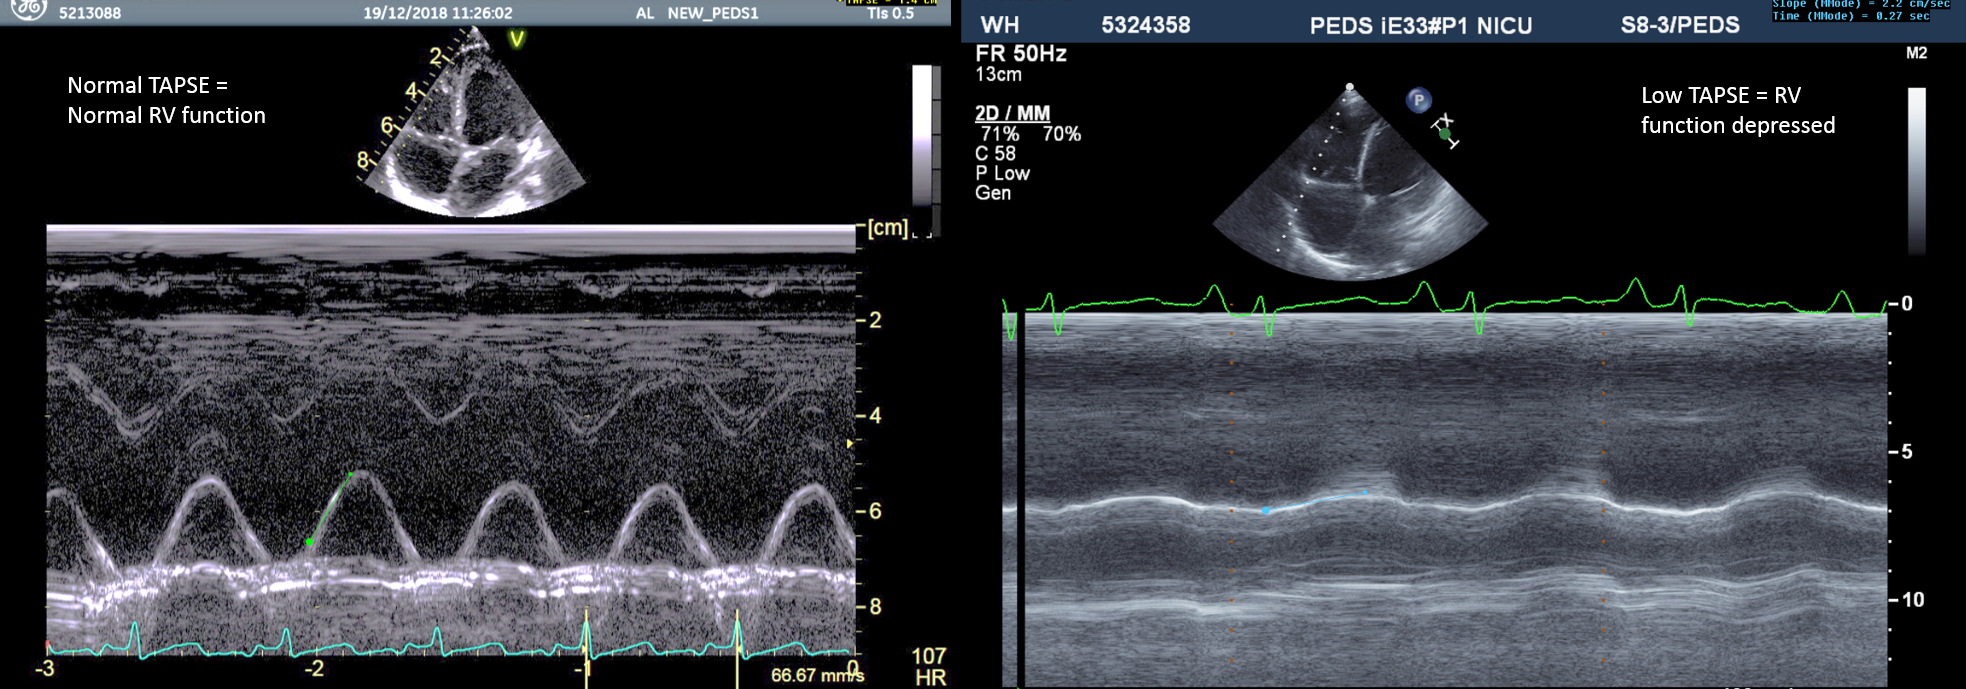

TAPSE (tricuspid annular plane systolic excursion) is easily obtainable and is a measure of RV longitudinal function. It is measured from 4-chambers view in M-mode at the level of the tricuspid annulus, and the value is in mm and represents the displacement of the TV annulus toward the apex in systole. TAPSE < 16 mm in adults indicates RV systolic dysfunction, values TAPSE in children depending of age and BSA.